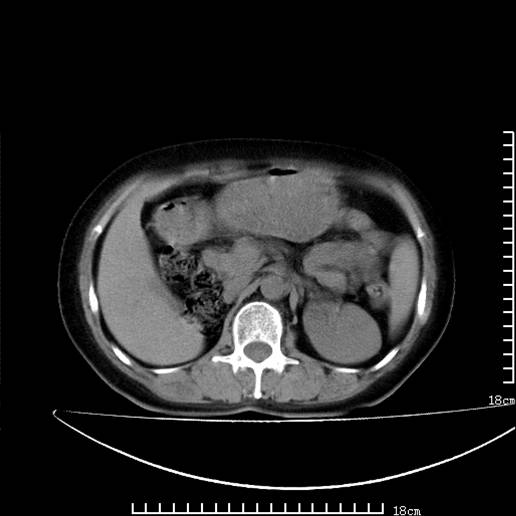

以下是引用pujunzhi在2008-5-30 15:31:00的发言:[br]异位肾—盆腔肾。当看到肾窝无肾脏时,要想到孤立肾和异位肾,异位肾最常见是盆腔肾,偶见胸腔,易误认为肺占位,只要想到就不会漏诊。建议增强扫描。